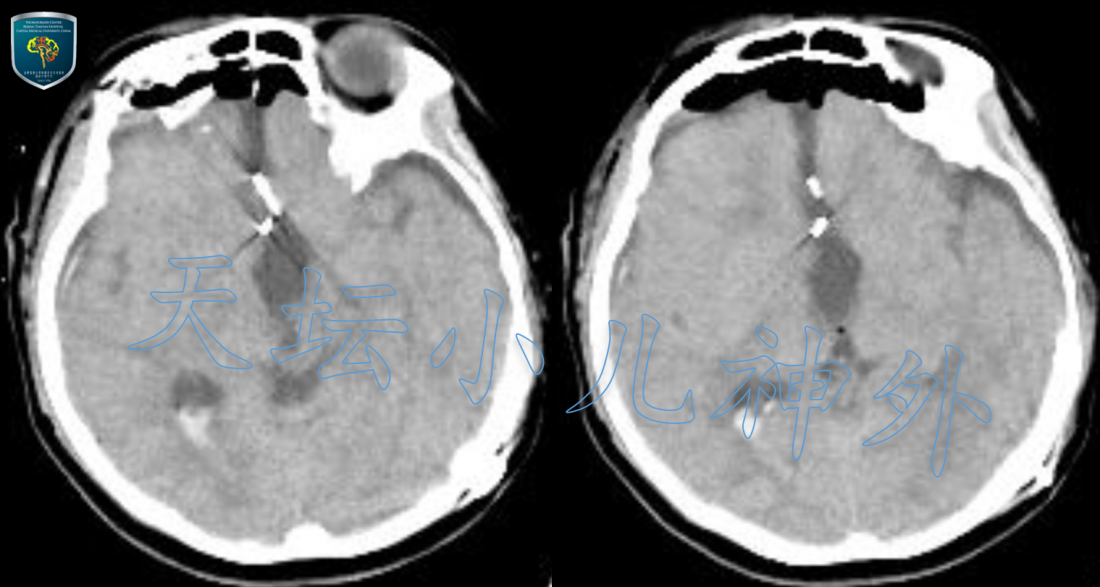

本例颅咽管瘤体积巨大,囊性主体突入第三脑室,第一间隙狭小,手术只能通过终板间隙(第四间隙)施行肿瘤切除。依据天坛小儿神外诊疗规范(附链接),先行Ommaya囊腔穿刺,囊液抽吸缓解梗阻性脑积水,待两周后瘤体缩小,瘤壁与下丘脑松解后再行手术,大大提高了手术安全性。